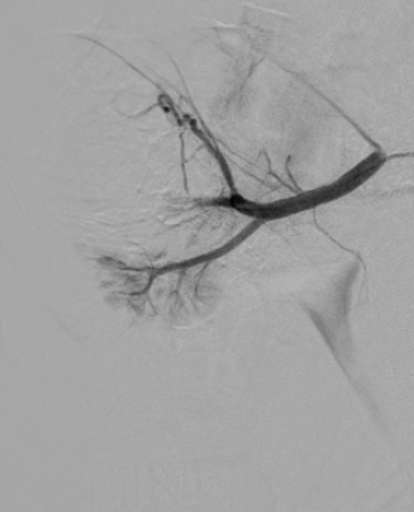

תמונות מההליך

שלבי הפעולה:

- סיום הצנתור – הפסקת זרימת הדם לגידול

- שמירה על רקמת הכליה הבריאה